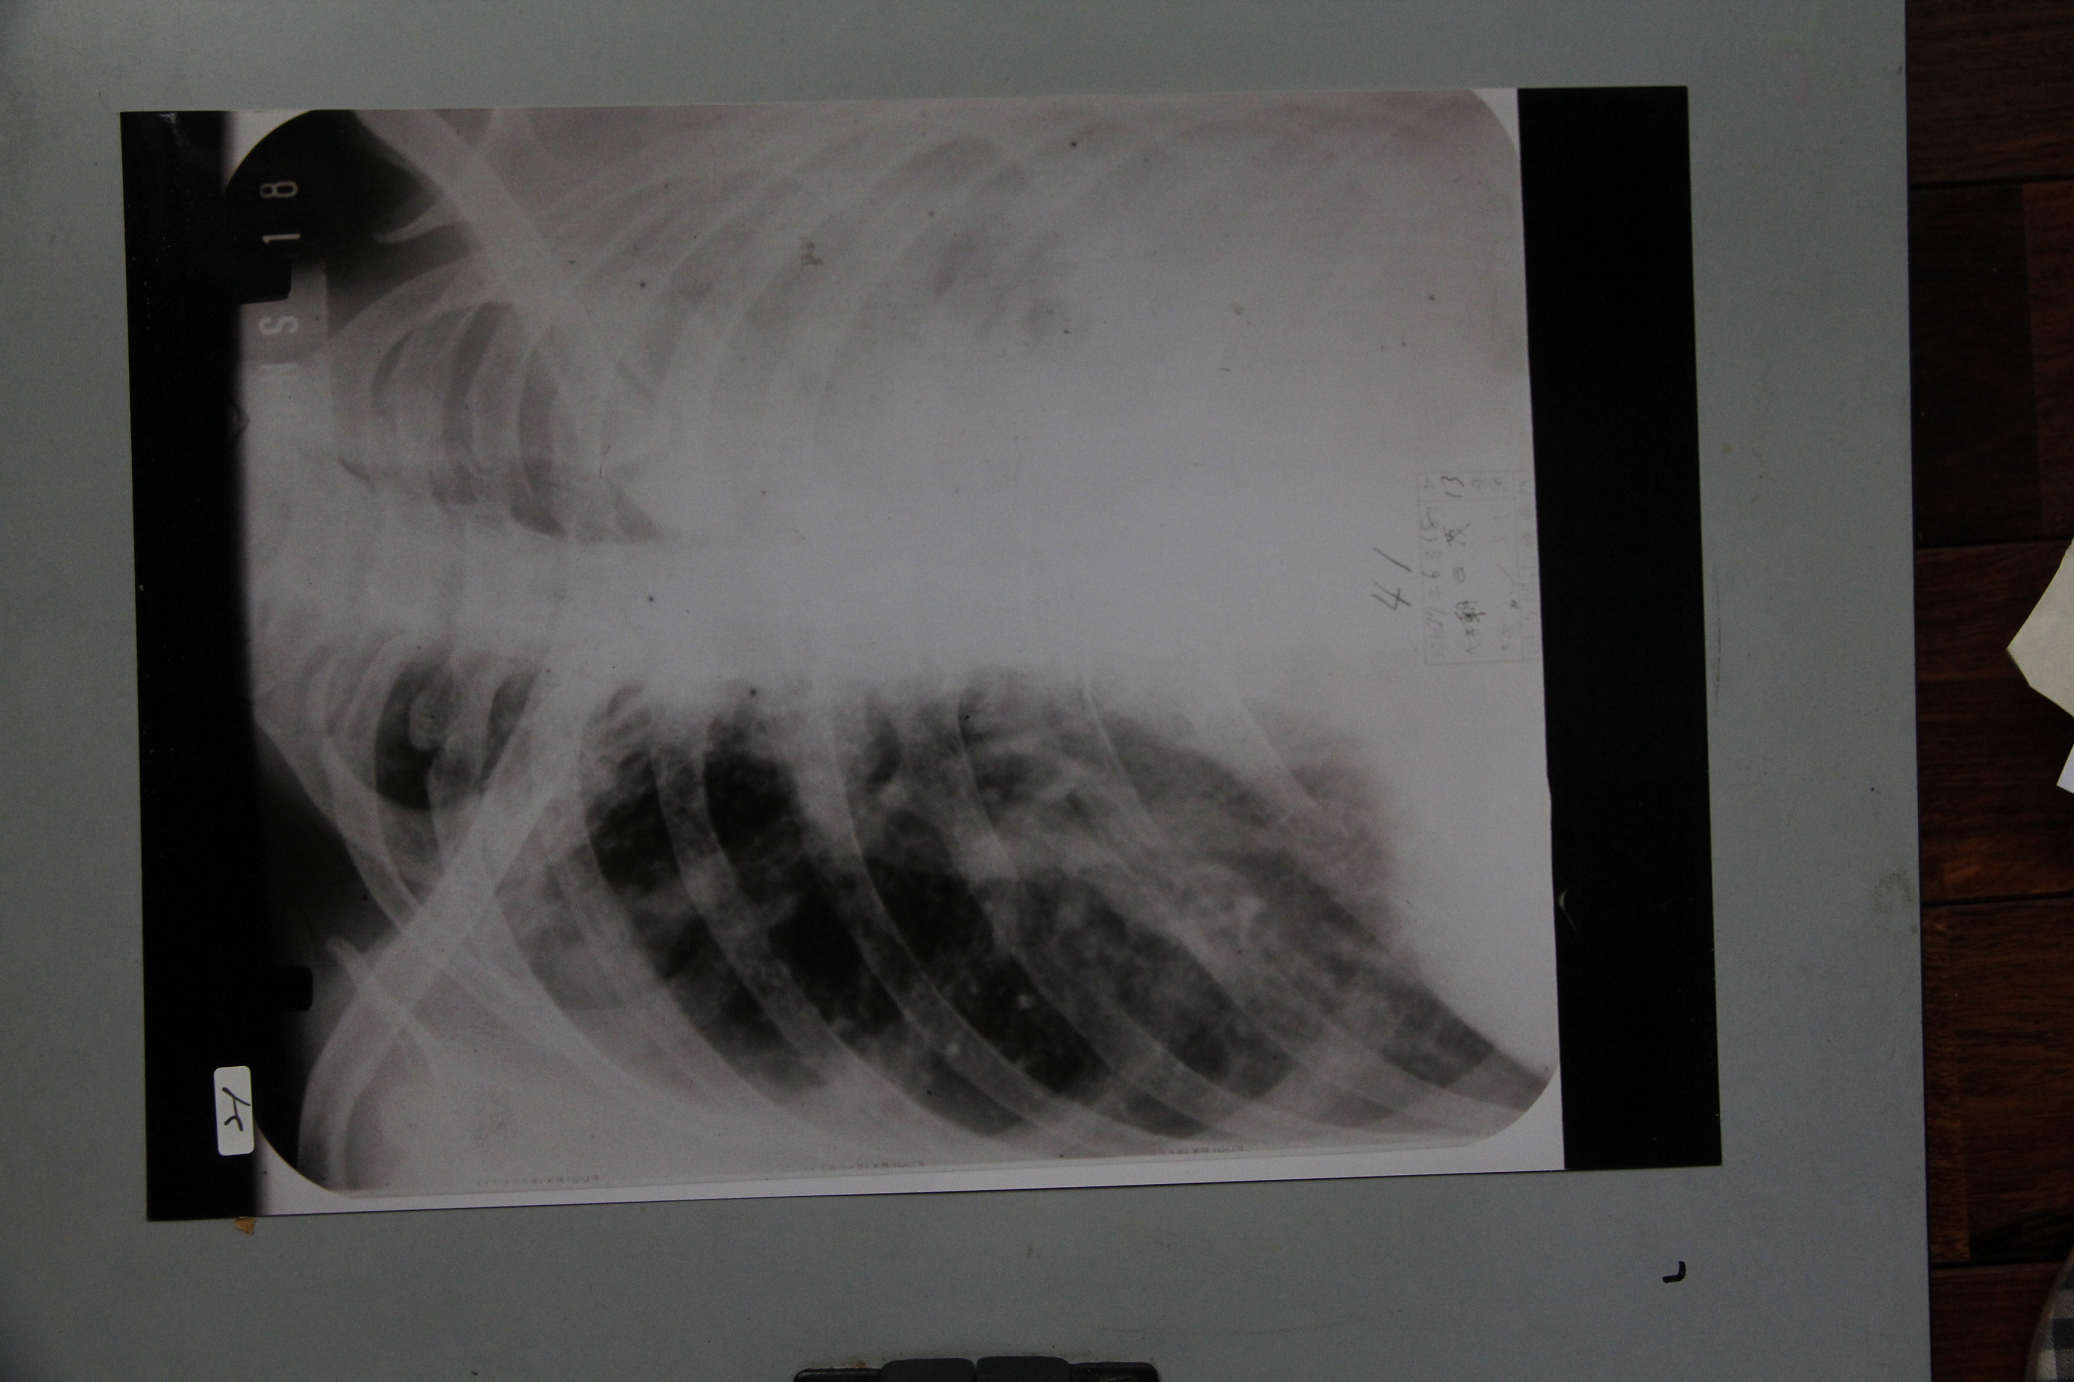

朝日茂胸部レントゲン写真

朝日茂胸部X線写真